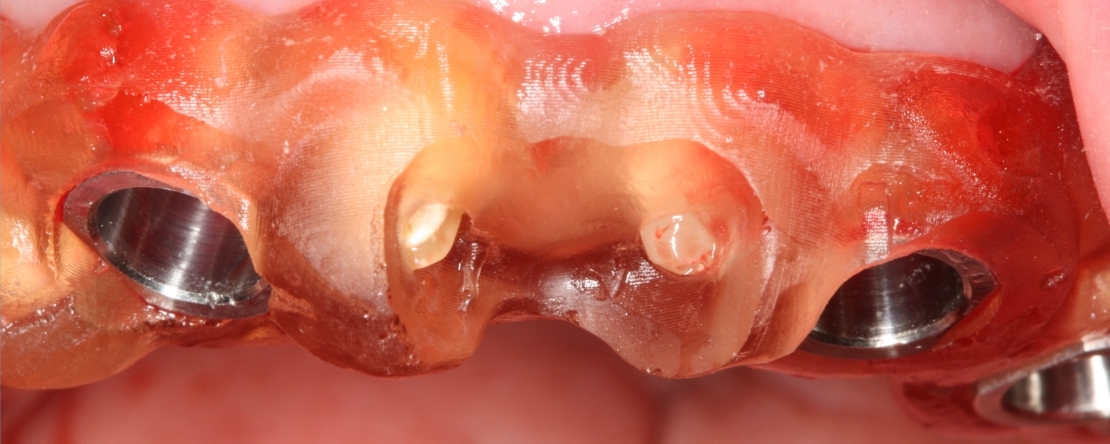

O facto de os médicos dentistas terem à sua disposição tecnologias digitais, como sejam as tomografias computorizadas de feixe cónico (CBCT), o scanner intra-oral, os softwares de desenho computadorizado, as impressoras 3D, coadjuvadas pela inteligência artificial, permite-lhes planificar a colocação de implantes guiada pela prótese, que é o objetivo último da intervenção clínica.

Nesta apresentação, irá ser apresentado o fluxo digital da “prosthetically driven implant surgery”, suportado por casos clínicos e pela última evidência científica publicada pelo “International Team for Implantology”.